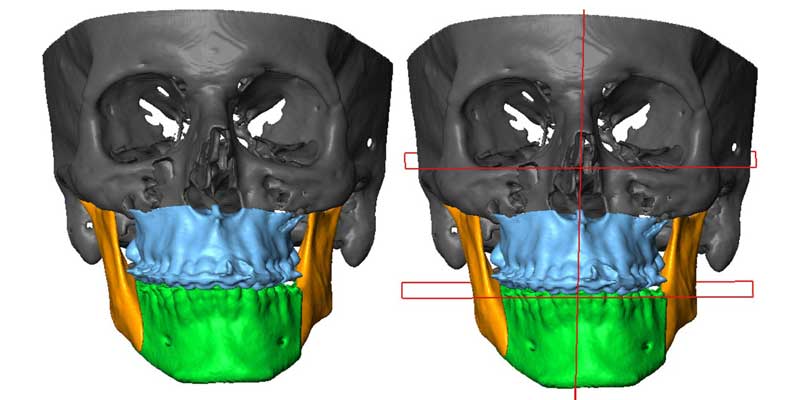

تصویربرداری:

عکس برداری رادیولوژی، سی تی اسکن یا ام آر آی می توانند اطلاعات دقیقی از ساختار استخوانی فک ارائه دهند.

اسکن دیجیتال سه بعدی:

برای بررسی دقیق تر و طراحی برنامه درمانی استفاده می شود.

- دو فک (Bimaxillary Asymmetry): عدم تقارن در هر دو فک که نیاز به بررسی دقیق تر دارد.

درمان ارتودنسی به همراه جراحی دو فک در اصلاح فک های نامتقارن شدید که نیاز به تغییر موقعیت هر دو فک دارند، استفاده می شود.